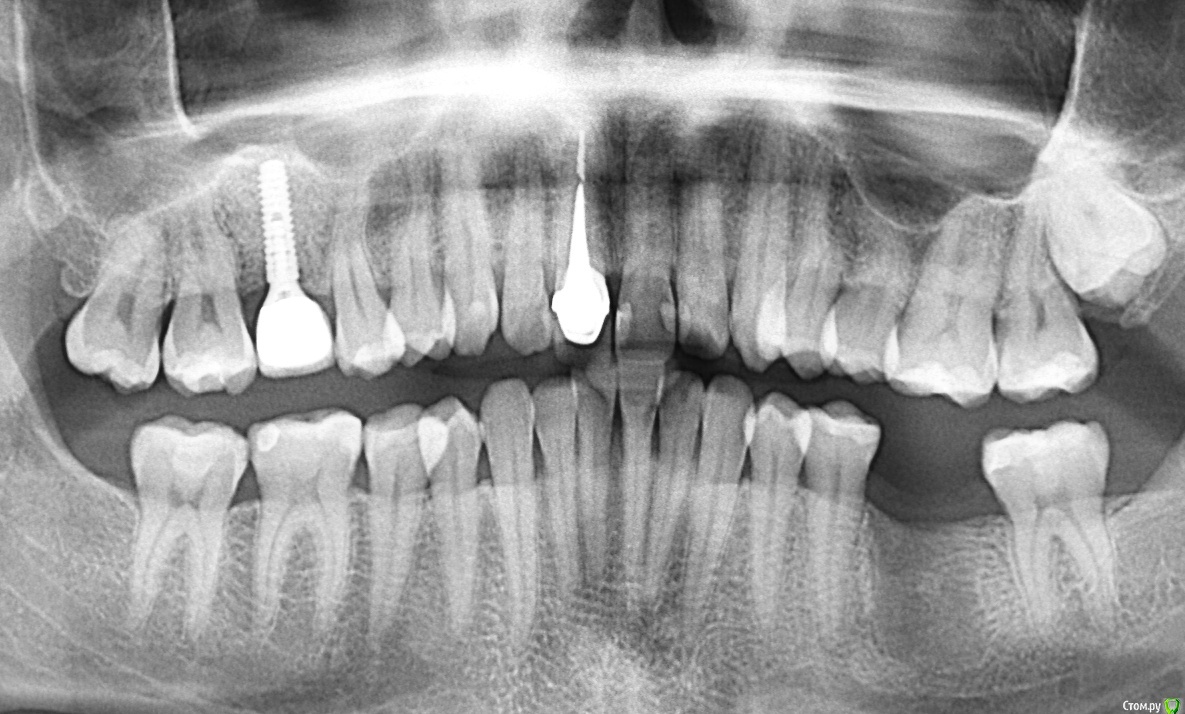

DenisB Опубликовано 13 октября, 2020 Автор Поделиться Опубликовано 13 октября, 2020 Нужно сделать рентгеновский снимок этой областиПрицельного снимка этого зуба на текущий момент нет, но есть актуальная ортопантомограмма. На ней этот зуб - второй справа в нижнем ряду. Будет ли её достаточно для ответа на мой вопрос или обязательно прицельный снимок? Ссылка на комментарий

red_butler Опубликовано 13 октября, 2020 Поделиться Опубликовано 13 октября, 2020 По фото и панорамному снимку не понятна стадия кариеса, я бы скорее вёл его как кариес дентина, то есть пломбировал Ссылка на комментарий